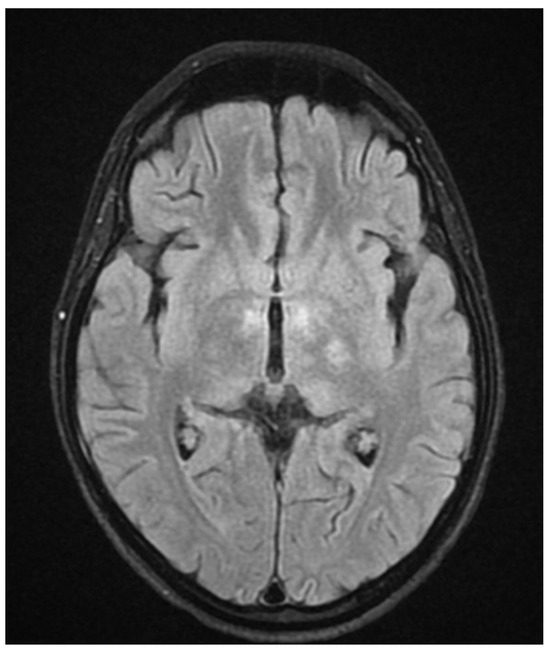

During hospitalization in the neurology ward, Holter EEG was performed in which seizure episodes corresponded to changes in the recording. Interictal EEG showed rapid activity followed by slow theta waves and several sharp and slow wave complexes (Figure 1 and Figure 2). Topiramate was added to valproic acid at a target dose of 2 mg/kg of body weight. Gradual seizure relief was observed in the following weeks, and there were no other neurological manifestations for another nine months. After that time, in December 2021, the patient was admitted to the pediatric ward due to impaired consciousness and persistent vomiting, followed by paresis of the lower limbs. A brain MRI was performed, which showed “T2/FLAIR images reveal poorly defined areas of increased signal in the brain’s white matter, both above and below the tentorium, as well as in the periventricular and subcortical regions. These areas correspond to low signal regions in T1 images. The largest change area measures 19 × 14 mm and is located in the right middle cerebellar peduncle, which merges with changes observed in the pons. Additionally, there is a lesion in the right thalamus, measuring 10 × 24 mm, along with numerous scattered foci in the corona radiata and between the basal nuclei. Overall, the imaging findings primarily suggest acute disseminated encephalomyelitis (ADEM)” (Figure 3 and Figure 4). Cerebrospinal fluid examination revealed oligoclonal bands and an elevated protein level of 118.5 mg/dL (reference range: 15.0–45.0 mg/dL) and a slightly elevated leukocyte level of 29/mm3 (lymphocytes 72.4%, neutrophils 27.6%).

Figure 3.

Transverse FLAIR brain magnetic resonance image showing numerous foci of increased signal between the basal nuclei (December 2021).